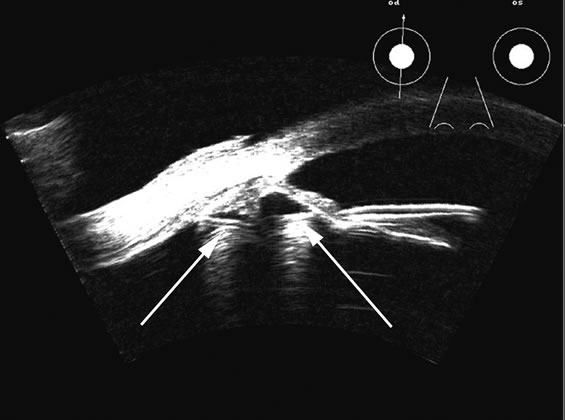

Fig. 5. An anterior chamber intraocular lens has had the support haptics dislocate posterior to the iris plane and can be seen as typical foreign body echogenic reflections (arrows).